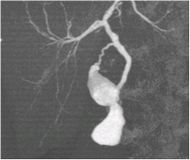

造影CT冠状断像(胆嚢がん)

造影CT矢状断像(胆嚢がん)